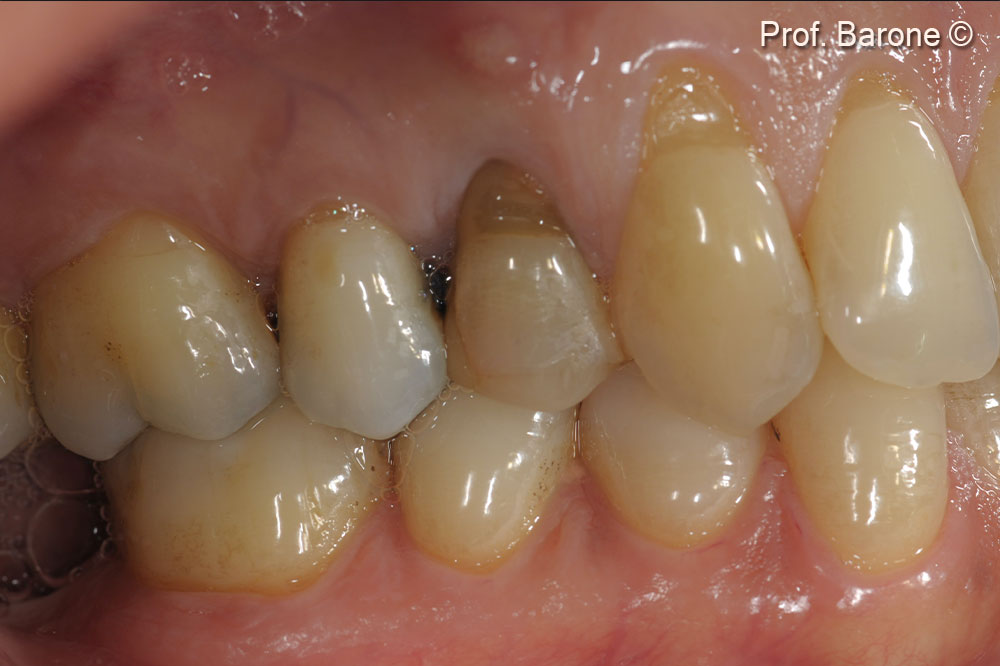

Clinical lateral view 6 weeks after final crown delivery